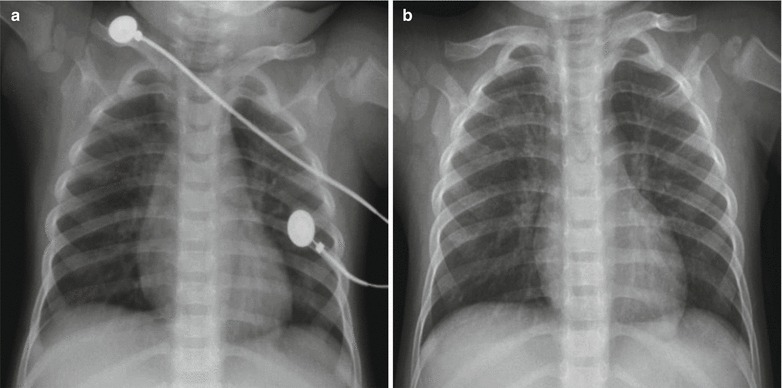

Fig. 23.14.

Pediatric measles complicated by pneumonia and pulmonary atelectasis. (a) X-ray demonstrates flakes of shadows in both lung fields along with the pulmonary markings, large flakes of high-density shadows in the right upper lung with clearly defined inferior boundaries, upward shift of the interlobar fissure, and blurry hilar shadows at both lungs. By reexamination after treatment for 2 days, X-ray demonstrates progress of the conditions. (b) X-ray demonstrates enlarged range with lesions in the right lower lung

Fig. 23.15.

Pediatric measles complicated by pneumonia. (a) X-ray demonstrates large flakes of increased density shadows in both lungs with unclearly defined boundaries, and blurry hilar shadow of both lungs. (b) By reexamination after treatment for 2 days, X-ray demonstrates no obvious change of the lesions. (c) By reexamination after treatment for 5 days, X-ray demonstrates enhanced and blurry pulmonary markings of both lungs, multiple patches of shadows in both lungs, and clearly defined hilum. (d) By reexamination after treatment for 9 days, the lesions are demonstrated to be further absorbed and improved